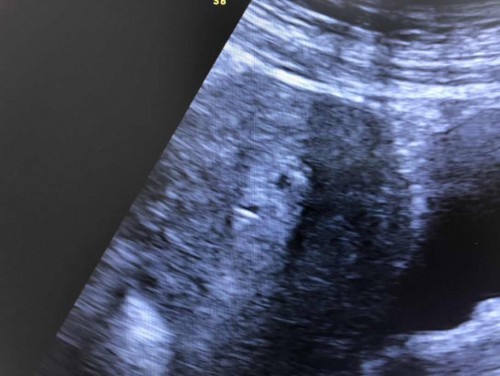

สอบถามหน่อยค่ะ พอดีไปอัลตราซาวด์มา

หมอยังไม่ระบุอายุครรภ์ นัดอีกทีศุกร์หน้าคะ แต่ค่า hgc อยู่ที่ 962 ค่ะ แต่เห็นในที่ซาว มี สองจุดด้วย ไม่ได้ถามคุณหมอ มีโอกาสเป็นแฝดมั้ยคะ

ซาวผ่านหน้าท้องหรอคะแม่ จุดเล็กมากๆเลย